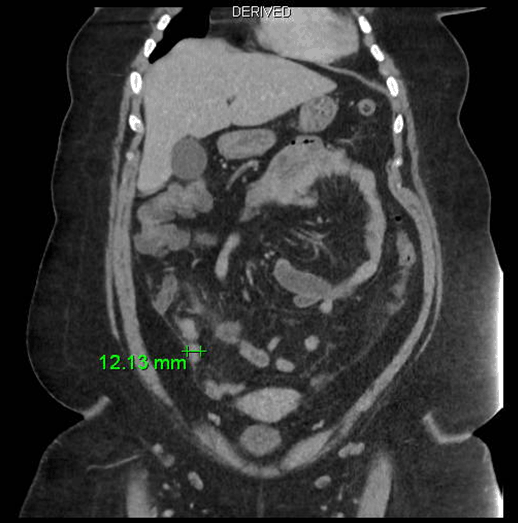

A 16-year-old girl presented with swelling in the right lobe of thyroid. There were no generalized symptoms like fever, malaise, night sweats and weight loss. There was no history of difficulty in deglutition or voice change. On clinical examination there was a single abscess of size 4x4 cm in right lobe of thyroid moving with deglutition. The margins were well demarcated, smooth surface, non-tender and overlying skin was normal with a tattoo mark on it (Figure 1). There were no clinical features of hypothyroidism or hyperthyroidism. Routine blood investigations were done; hemoglobin 11.0 g/dl, total leucocytes count 8600/mm3, neutrophils 67/mm3, lymphocytes 31/mm3 and eosinophils 2/mm3. The erythrocyte sedimentation rate was 20 mm. The Mountax test was highly positive more than 10 mm in diameter. Thyroid function tests T3, T4, TSH were normal. X-ray chest was normal. Ultrasonography of neck revealed a 50x45x20 mm solitary nodule in the right lobe of liver. This solitary thyroid nodule was showing thick irregular wall with central necrosis reported as suspected thyroid abscess. Magnetic resonance imaging scan of the neck showed a lesion of intermediate signal intensity due to presence of dense inflammatory cells and granulomas with central necrosis (Figure 2). A doubt about carcinoma of thyroid was placed as differential diagnosis. The CECT scan of neck was done to rule out carcinoma of thyroid gland. This was helpful in diagnosis of tubercular thyroid abscess as localized caseous lesion in right lobe of thyroid (Figure 3). Fine needle aspiration from this solitary thyroid nodule was done to confirm the diagnosis. The stained smears revealed degenerated and intact neutrophils, and macrophages in serofibrinous background. A few epithelioid granuloma and multinucleated giant cells are also seen suggestive of tuberculosis with central caseous necrosis. Ziehl–Neelsen staining with 20% H2SO4 was noncontributory (Figure 4). From the central part of swelling about 2 ml of thick yellow color pus was aspirated as shown in Figure 5. The smears prepared from this pus did not show any acid-fast bacilli. After aspiration the swelling decreased in size. The cytological diagnosis of tubercular abscess was made. The patient was put on antitubercular treatment with four drug regimens. The swelling decreased in size in next three months (Figure 6). She was asked to continue on three drug regimens for another six months leading to complete resolution of swelling. | ||||||